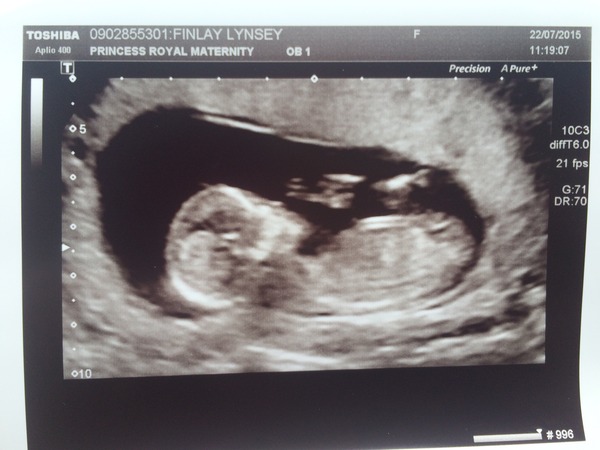

It's a baby!!!! ???????? Smile

It was the most amazing feeling ever seeing it on the screen!!! So happy!! It was so clear! Everything was fine and healthy. Now 13+1 due 26th of January xxx